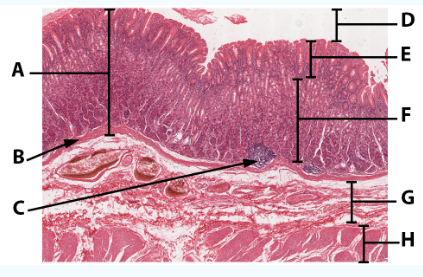

A

Mucosa

B

Muscularis mucosa

C

MALT

D

Lumen

E

Gastric pits: simple columnar epithelium

F

Gastric glands

G

Submucosa

H

Muscularis externa: oblique, circular, and longitudinal

area

Stomach